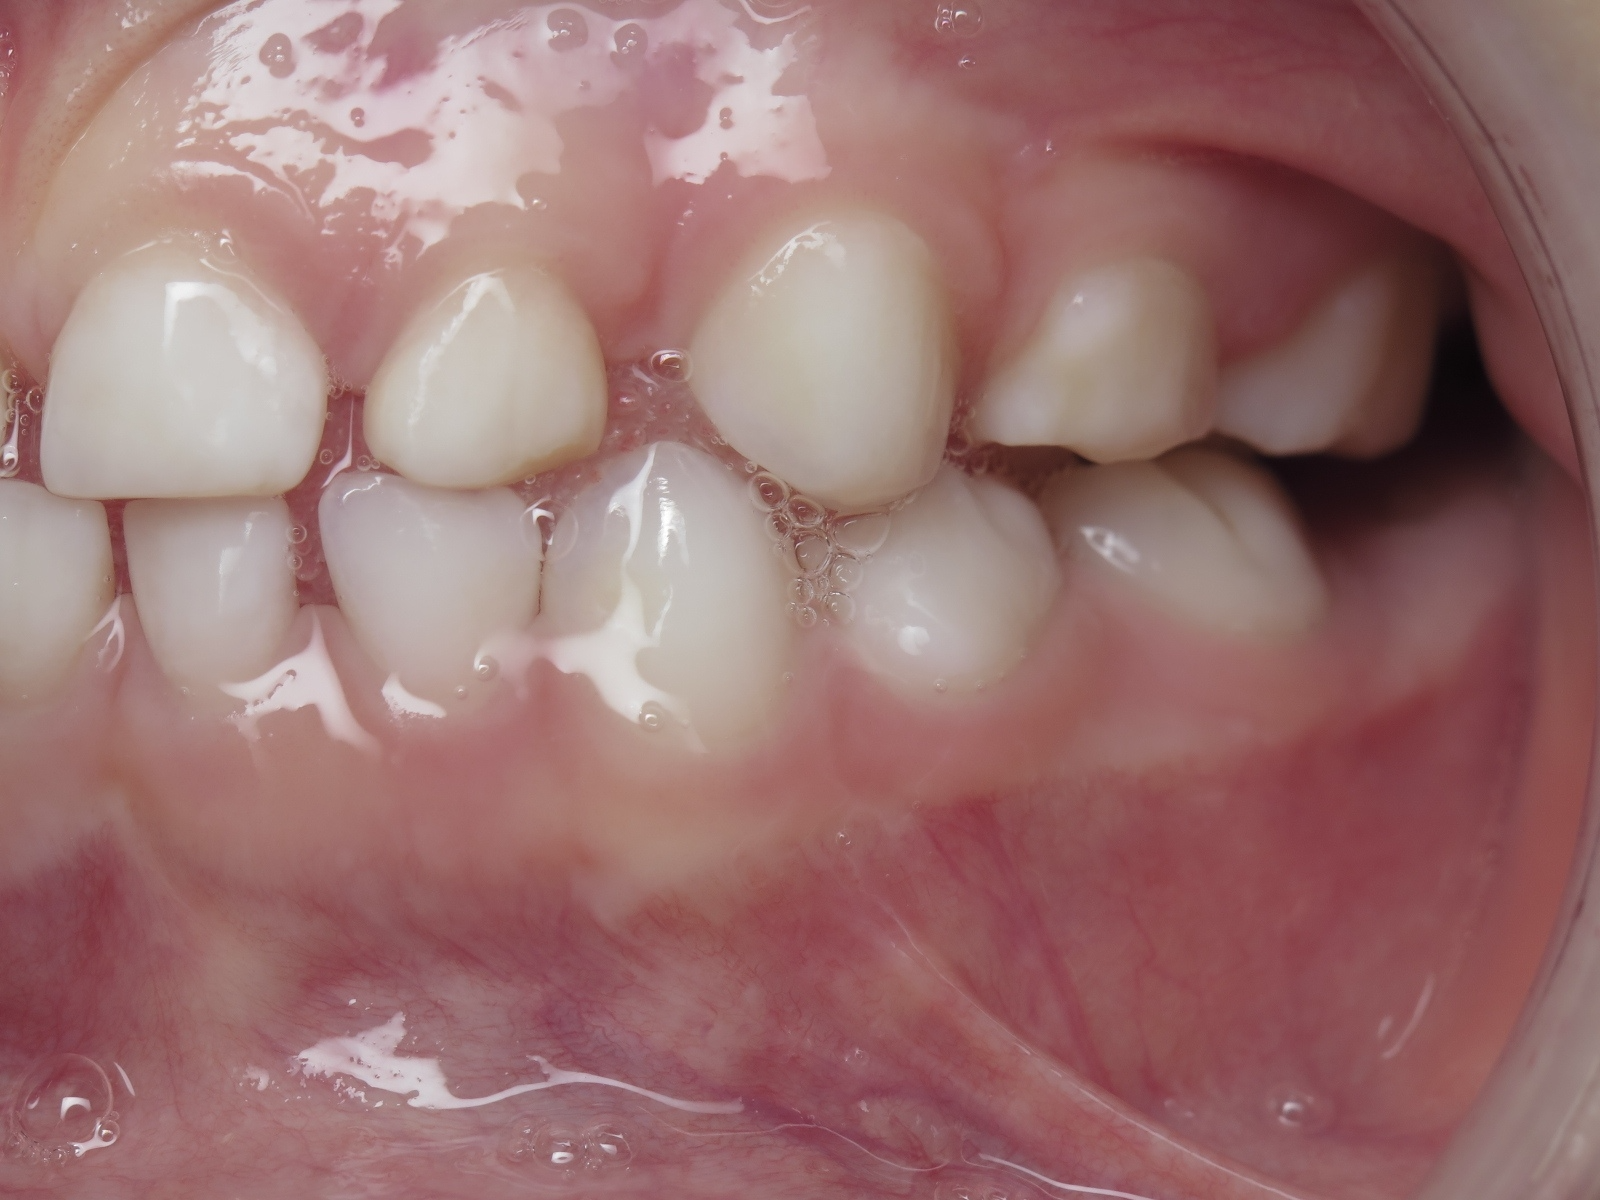

appareillage mobile pendant 13 mois

surveillance de la dentition pendant 16 mois

bilan début et en cours de traitement